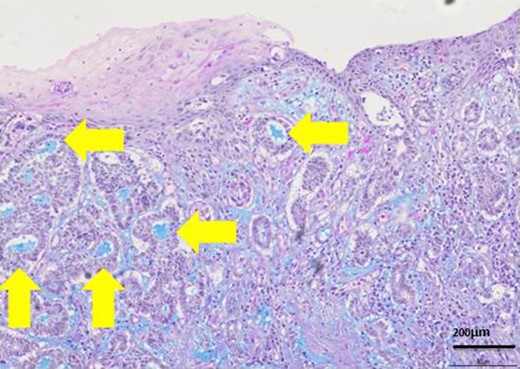

Most lumens had mucus which was stained blue by AL-B and PAS stain (yellow arrows). It showed lumens had acid mucopolysaccharide like sialomucin.

The patient was an 83-year-old male with a granulomatous tumor on his left lower leg. He said that it had existed for about 10 years. An incisional skin biopsy was performed at a neighbor medical institution and histopathologically suggested PCACC. He was introduced to our out-patient clinic. At his admission, the tumor was about 4 cm in the diameter and showed a few red granulomatous nodules (Fig. 1). MRI revealed that the tumor infiltrated subcutaneous tissue but did not reach muscle and bone (Fig. 2). The whole-body PET-CT showed that fluorodeoxyglucose (FDG) accumulated at the tumor area of the left lower leg. FDG also accumulated in the left inguen, however any other accumulation was not defected (Fig. 3). Therefore, it was suspected that the left inguinal hot spot was the metastatic lesion from the PCACC lesion at the left lower leg. At the first operation, the tumor was resected 2 cm far from the tumor margin, including basal muscle fascia and periosteum, and the defect was covered with an artificial dermis under general anesthesia (Fig. 4). At the same time, inguinal lymph node dissection was performed. Histopathological examination of the tumor revealed that cubical cells which had high nuclear-to-cytoplasmic ratio proliferated with cribriform, tubular or cord-like structure in the dermis and subcutaneous tissue. Perineural invasion by the tumor was observed. Metastasis to superficial inguinal lymph node was also histological confirmed (Figs 5 and 6). Most lumens had mucus which was stained by Alcian-blue (AL-B) and Periodic acid-Schiff (PAS) inside of them (Fig. 7). In the immunohistochemical findings, the tumor cells were positive for EMA, SMA, S-100protein, BerEP4, p63 and C-kit (Fig. 8). According to these clinical and pathological findings, the tumor was finally diagnosed the tumor as PCACC. Microscopically, the tumor was resected completely.